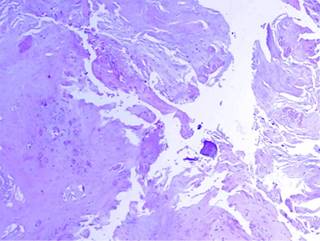

Figure 4: There are areas of calcification immersed in the elastic fibers, which are seen round, basophilic and concentric, which resemble bodies of psammoma.